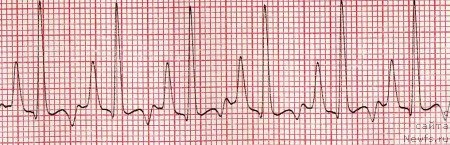

На ранних стадиях болезни ЭКГ может оставаться без изменений. У пород склонных к нарушениям ритма в начале болезни регистрируют редкие желудочковые экстрасистолы. В нашей практике встречались случаи выявления мерцательной аритмии уже на ранних стадиях развития патологии. При значительном ремоделировании сердца обнаруживают признаки увеличения левого желудочка: большая амплитуда зубцов R в отведениях I, II, III, V4, V2. При нарушениях внутрижелудочкового проведения зубцы R могут быть зазубрены. При выраженных фиброзных изменениях миокарда или наличии плеврального и/или перикардиального выпота амплитуда зубцов комплексов QRS может быть снижена. При увеличении левого предсердия в два и более раз на ЭКГ появляются зубцы Р-mitrale, которые расширены более 0,05 сек. При развитии значительной легочной гипертензии на ЭКГ регистрируют признаки увеличения/перегрузки правого предсердия – высокоамптитудные (боле 0,4 мВ) зубцы Р –pulmonale (рис. 2) и глубокие (более 0,8 мВ) зубцы S (особенно в отведениях V4 и V2).

Рис. 2. Высокие заостренные зубецы Р (р-pulmonale).